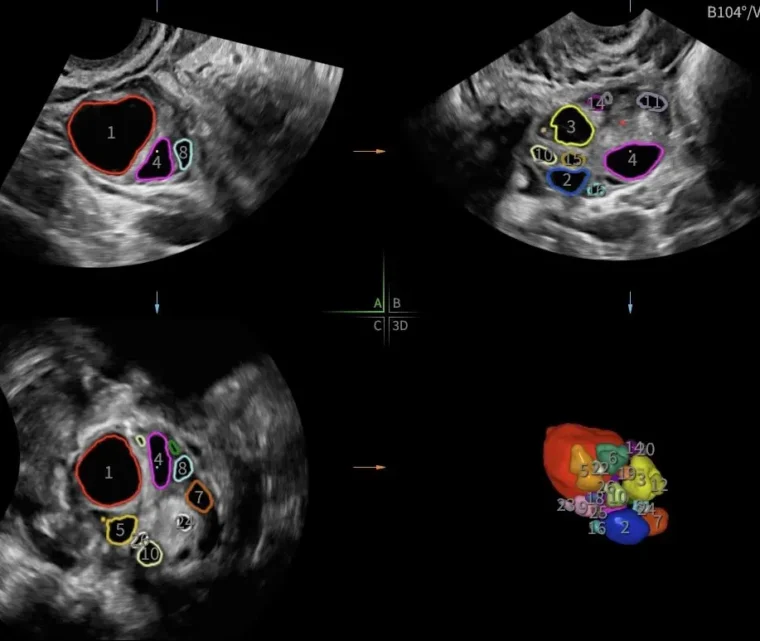

Ovaries: The scan assesses the size and presence of cysts. During the assessment, we will assess the number of antral follicles and follicle sizes.

Ovulation Tracking

One of ultrasounds best abilities is to look at how your eggs are growing. This may be done for

It involves an internal ultrasound to measure the number and size of the follicles in each ovary. The first scan will often occur several days before ovulation is expected and continue every 2-3 days until the follicles (eggs) are the correct size for your specific fertility treatment.